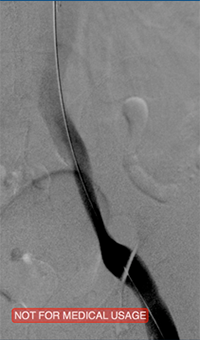

xray image of Iliac vein post-ZelanteDVT.

Iliac vein post-ZelanteDVT

xray image of liac vein post-PTA & stent.

Iliac vein post-PTA & stent

Femoral vein post-ZelanteDVT.

Femoral vein post-ZelanteDVT

Images courtesy of Jeffrey Y. Wang, MD FACS, Vascular Surgeon; Horizon Vascular Specialist, Maryland.  November, 2015